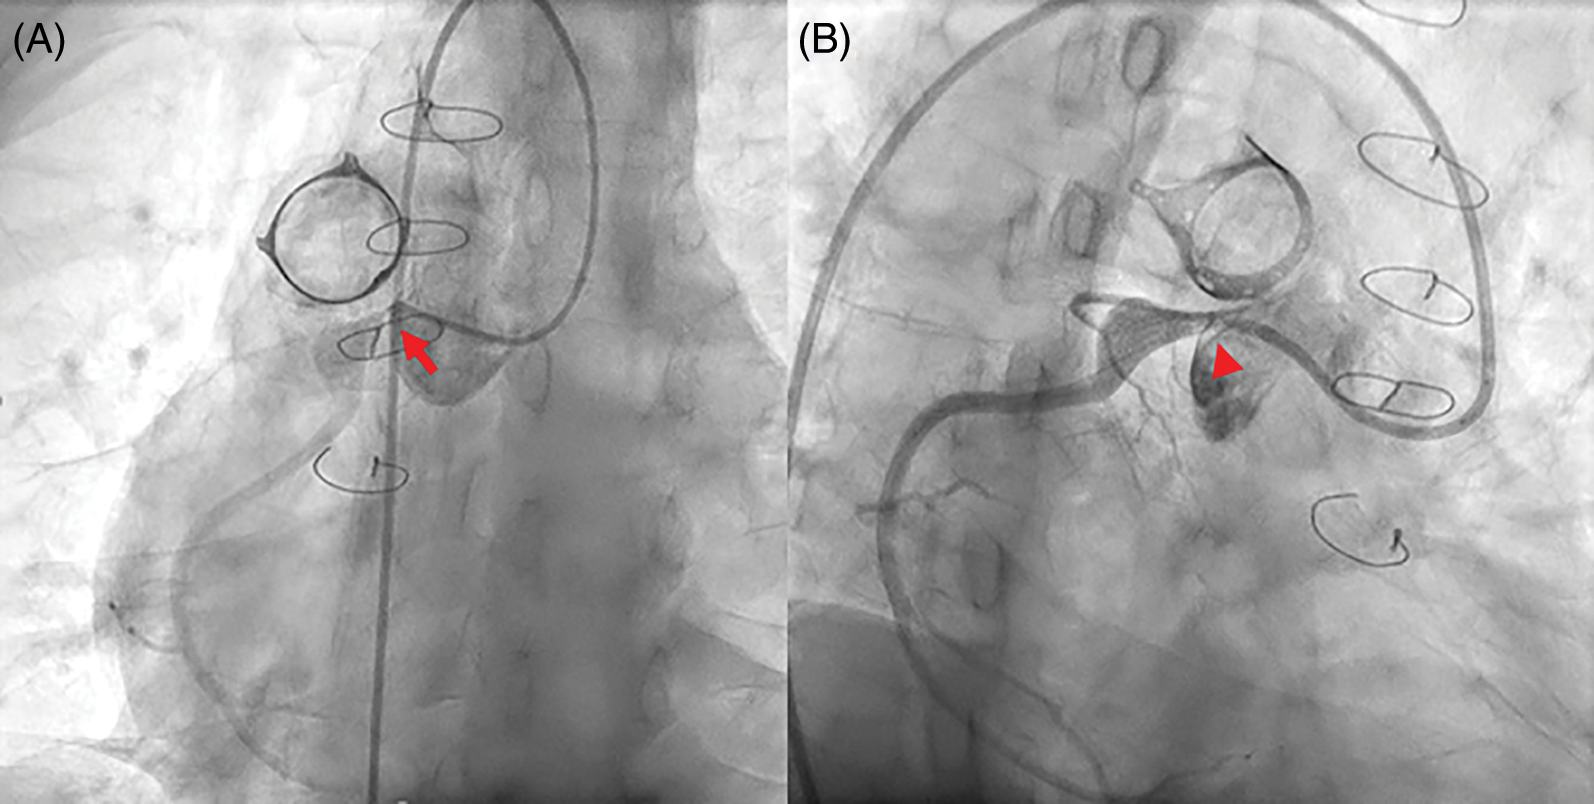

Four patients complained of atypical chest pain, of whom three had ventricular dysfunction and non-sustained VT on Holter monitoring. The other one patient was a 39-year-old man (patient 8) who visited the emergency department with atypical chest pain at 33 years after the RVOT reconstruction surgery. Even though ECG showed no ST-T change, echocardiography revealed normal ventricular function, and cardiac enzymes were within normal ranges; ICA showed severe RCA ostial stenosis adjacent to the conduit and aneurysmal dilatation of proximal RCA (Fig. 4A). Percutaneous coronary balloon angioplasty and drug-eluting stent insertion was performed with Resolute Onyx™ (Medtronic Inc., Santa Rosa, California, USA) 2.75 × 12 mm, and the stenosis was improved (Fig. 4B).

Figure 4: Percutaneous coronary intervention in patient 8 who performed Rastelli procedure for transposition great arteries and pulmonary stenosis.

Note: (A) Selective right coronary angiography showing severe right coronary artery ostial stenosis (red arrow) adjacent to the conduit and aneurysmal dilatation of the proximal portion. (B) After percutaneous coronary intervention, the stenosis is improved (red arrowhead).